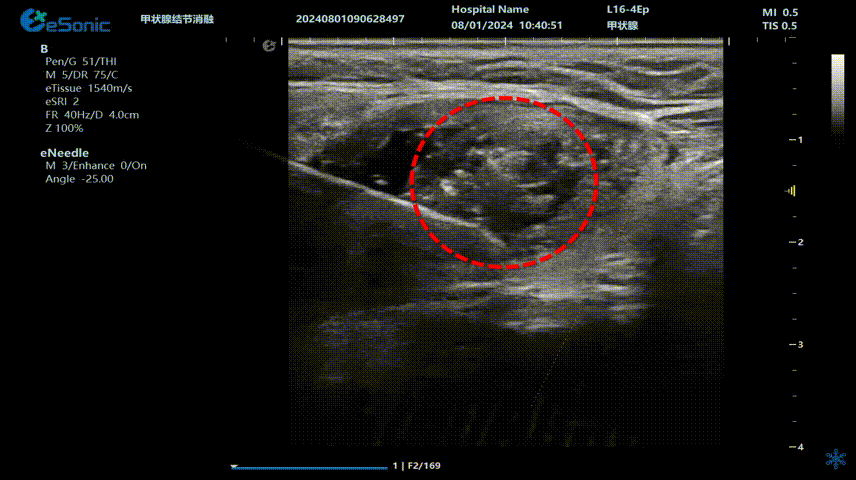

治疗当天,超声介入科董刚教授将一根细细的消融针穿刺到甲状腺结节内,通过针尖产生热量,高温加热作用可以使结节病灶组织被精准灭活,最后坏死组织随着时间的推移逐渐被身体吸收,直至消失。

640 (3) (2).gif

(甲状腺结节射频消融动态视频)

李女士接受了甲状腺射频消融手术,过程顺利,手术耗时约20分钟,患者无出血、声音嘶哑等并发症。术后生命体征正常,观察几小时后便回家休息。次日恢复正常生活,颈部几乎看不到明显伤口。复查时显示甲状腺结节缩小,吞咽异物感消失。术后李女士摸着几乎无痕的颈部笑到:“没想到20分钟就解决了困扰我几年的问题!为微创射频消融技术点赞!”